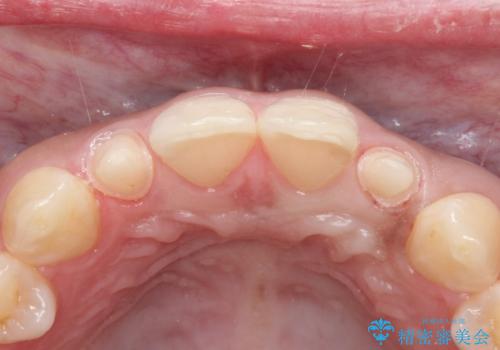

- 側切歯が小さいことを主訴に来院されました。

いくつかの治療の選択肢を説明し、オールセラミッククラウンで治療することとなりました。

長期的に安定した治療を求める場合はオールセラミッククラウンによる治療を提案します。